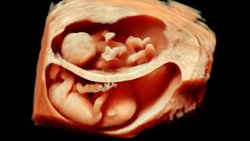

Aşağıda gördüğünüz, iki sıra bebek fotoğrafı. Bu fotoğrafları özel kılan şey, 4 boyutlu ultrason (3 boyutlu çekim + zaman) yöntemiyle kaydedilmiş olmaları. Ancak sadece bu da değil... Üstteki sıra, annesi sigara içen bir fetüse ait. Alttaki ise içmeyene...

İlk etapta çok fark görülemeyebilir. Ancak fotoğraf serisini soldan sağa doğru dikkatle takip edecek olursanız, üstteki bebeğin ağzını yüzünü hareket ettirdiğini ve eliyle yüzüne dokunmaya çalıştığını göreceksiniz. Alttakinin yüzü ise normal bir şekilde durmaktadır ve elleriyle yüzüne dokunma çabası yoktur.

"Ee, ne var bunda?" diyebilirsiniz... Sorun şu ki, bebekler hamileliğin erken evrelerinde yüzlerini buruşturmaya ve elleriyle yüzlerine dokunmaya meyillidirler. Bu normaldir. Ancak hamilelik süresi ilerledikçe, bu davranışlar giderek azalır ve bebek daha ziyade kollarına bacaklarına ve vücudunun geri kalanına dokunarak özellikle uzuvlarını tanımaya çalışır. Bunun nedeni, sinir sistemi ve beyni geliştikçe, uzuvlarını daha aktif olarak kullanmaya başlamasıdır. Yüzüne olan ilgisi azalır. Dahası, yüzünü de buruşturmayı bırakır.

Fakat Durham Üniversitesi tarafından yapılan yeni bir araştırmada, hamilelikte sigara içen annelerin yavrularında bu gelişim evrelerinin yavaşladığı gözlendi.[1] Yani üstteki seride, bebek aslında artık bırakmış olmasına rağmen yüzünü buruşturmaya devam ediyor ve yüzüne dokunmaya çalışıyor. Alttaki seride (sigara içmeyen anneni bebeği) ise normal gelişim görülüyor. Uzmanlar bu farklılığı sigaranın sinir sisteminin gelişimi üzerindeki yavaşlatıcı ve olumsuz etkiye bağlıyor.